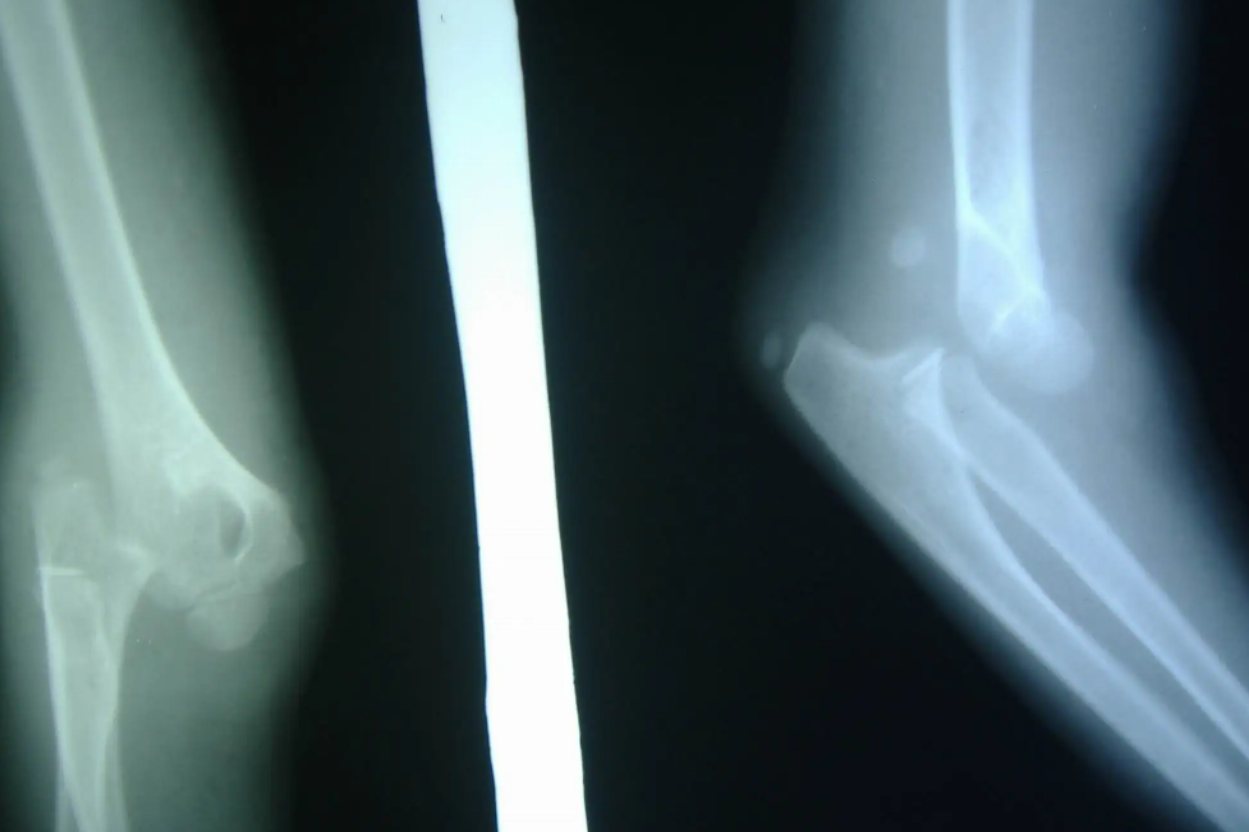

肘关节脱位:

肘关节部位疼痛、活动障碍,肉眼可见或用手可触及肘关节向后或是向侧边突出,肘后三角关系异常。